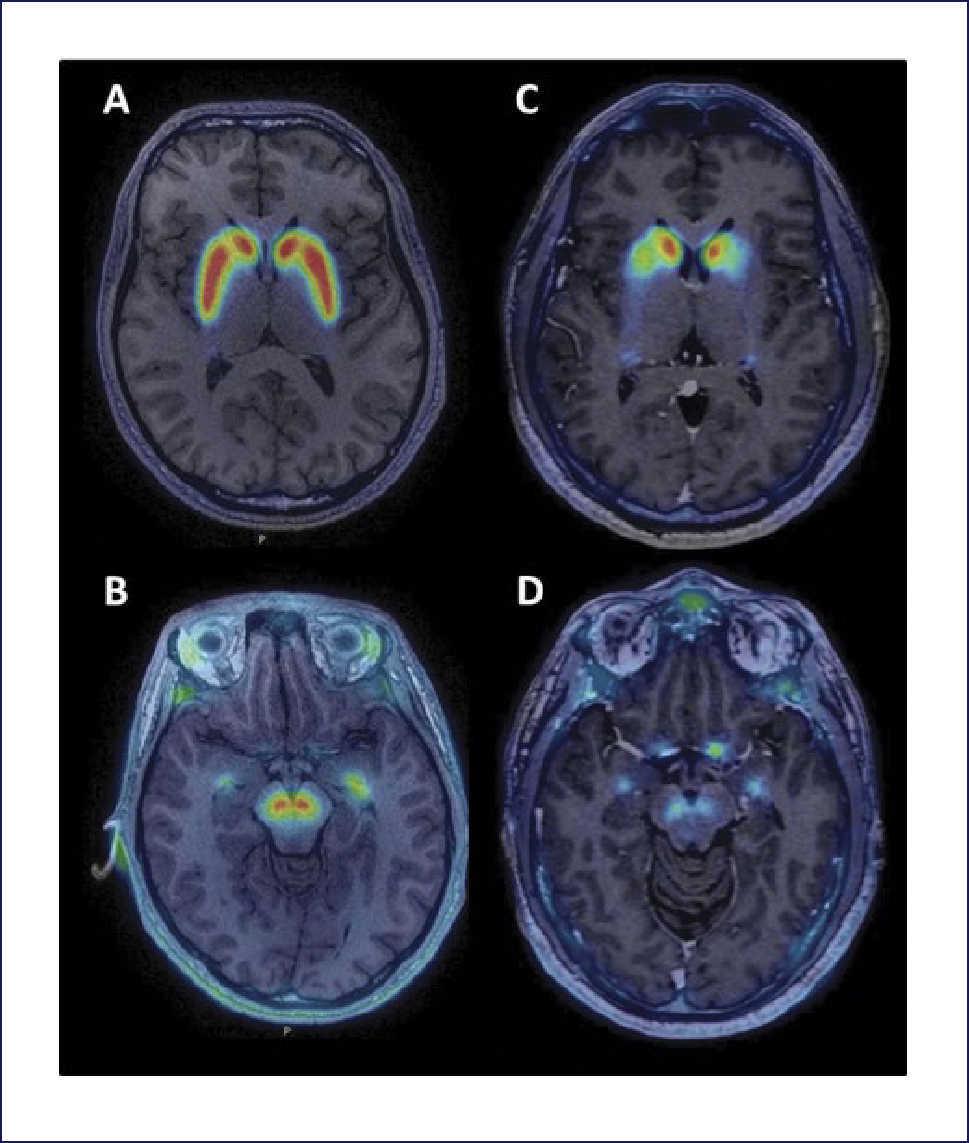

Engineer Team : RESONANCIA MAGNETICA Magnetic Resonance Imaging – Clinical Images Hallazgos por resonancia magnética cerebral de nuestro paciente. M, 21 … Imágenes por resonancia magnética anormales como predictoras de mal … Imágenes por resonancia magnética anormales como predictoras de mal … Lesiones en resonancia magnética (RM) del encéfalo y la médula espinal … Pin en Resonancia Magnética del Encéfalo A) Resonancia magnética cerebral (RMC) mostrando infartos en … Caso 1: Edema cerebral visualizado mediante RM. (A) Secuencia T1 plano … Rascacielos dormir pasta tac y resonancia diferencias retrasar … Pin on Apuntes de Enfermería y T.C.A.E Resonancia magnética cerebral secuencia T2, que muestra lesión … Meningitis aguda en la enfermedad de Behçet | Reumatología Clínica Resonancia magnética coronal normal del cerebro Fotografía de stock – Alamy Imágenes de resonancia magnética, la imagen de la cabeza en diferentes … Resonancia magnética cerebral A) protocolo T1 sagital (Caso 1). Se … Resonancia magnética cerebral. Secuencia T1 corte sagital. Atrofia … Resonancia magnética de cerebro, cortes axiales, secuencias T2. Señal … Resonancia magnética de cráneo. A y B) Cortes axiales FLAIR … Resonancia magnética (RM) de cerebro, corte axial ponderado en T2: la … RM cerebral: Interpretación paso a paso | Kenhub Resonancia magnética de cerebro, cortes axiales, secuencias T2. Señal … De Resonancia Magnética De Cerebro Foto de archivo – Imagen de arteria … Top 107+ Imagenes de resonancia cerebral normal – Destinomexico.mx -Imagen por resonancia magnética del cerebro. a) Cortes sagital y axial … resonanCia magnétiCa Cerebral donde se observa hiperintensidad a nivel … MRI (Imagen de resonancia magnética) – Tomografía computarizada de la … Meningioma – NCI Imágenes por resonancia magnética coloreadas del cerebro sano del … Resonancia magnética cerebral en secuencia FLAIR, que muestra lesiones … Contraste resonancia magnetica cerebral – senturinthegreen Relación de los espacios de Virchow-Robin con la enfermedad de … Gliomatosis cerebral – Instituto Nacional del Cáncer Pin en Neurology. Recomendaciones para la utilización e interpretación de los estudios de … Fotografía De La Proyección De Imagen De Resonancia Magnética Del … atmósfera Dirigir Cumplir anatomia resonancia magnetica Desarrollar … Pin en #MEDICINA,#SALUD Resonancia magnética de la nasofaringe De Resonancia Magnética De Cerebro Foto de archivo – Imagen de polilla … Atrofia cortical global de predominio parietal en la Resonancia … Resonancia magnética cerebral | Download Scientific Diagram Neuroblog: Resonancia magnética cerebral en la trombosis crónica de … De Resonancia Magnética De Cerebro Imagen de archivo – Imagen de … ¿Cuáles son los riesgos de la resonancia magnética? – Integra Salud … Resonancia magnética cerebral al decimocuarto día de ingreso: área … Resonancia magnética. Corte axial mostrando área infartada en el … Resonancia magnética cerebral del paciente AV evidenciando lesiones en … -Ressonância magnética de encéfalo mostrando múltiplas imagens … Resonancia magnética cerebral secuencia FLAIR (Fluid Attenuated … Resonancia magnética cerebral con protocolo de epilepsia, en sección … Resonancia magnética cerebral en corte sagital. Se observa una evidente … Resonancia magnética craneal en la que se evidencian lesiones … Logran visualizar el cerebro a detalle más completo tras una resonancia … Así decide el cerebro la severidad de un castigo De Resonancia Magnética De Cerebro, Imagen de archivo – Imagen de … A) Resonancia magnética cerebral; Secuencia Tof: oclusión de arteria … Un estudio asocia la ansiedad con la aparición rápida del Alzheimer IMÁGENES DE 18 F-PR04.MZ PET FUSIONADA CON RESONANCIA MAGNÉTICA … Imágenes por resonancia magnética anormales como predictoras de mal … Tumores de la región pineal – Instituto Nacional del Cáncer Epilepsia: una historia de voces y fantasmas | Neurología Contribución de las imágenes de resonancia magnética por tensor de … Resonancia magnética secuencia T2 plano coronal de quiste epidermoide … Resonancia Magnética Cerebral del paciente: a. Aumento de… | Download … Resonancia magnética cerebral 2022 Síndrome de hemiconvulsión-hemiplejía-epilepsia. Seguimiento de un caso … Enfoque Radiologico: La resonancia magnética permite detectar lesiones … Resonancia magnética craneal T1 con contraste que muestra angiomatosis … guidewiz – Blog Resonancia magnética cerebral, secuencia SWI. Ribete hipointenso en la … resonAnCiA mAgnétiCA de ColumnA Con gAdolinio. Corte sAgitAl en t1 de … SEMANA 12: FUNDAMENTOS DE RESONANCIA MAGNÉTICA NUCLEAR. INDICACIONES Y … DIAGNÓSTICO DE ESCLEROSIS MÚLTIP Magnetic resonance imaging of the brain – Alchetron, the free social … Resonancia magnética de órbitas | Instituto Radiológico Dr. E Castillo Alteración de la marcha en un paciente post-trasplante hepático Resonancia magnética cerebral de un paciente sano (Ay B) y paciente que … Utilidad de la resonancia magnética craneal para el diagnóstico de la … Resonancia Magnética Del Cerebro El Tumor Cerebral Foto de stock y más … De Resonancia Magnética De Cerebro Imagen de archivo – Imagen de … ABDALLA RADIOLOGIA: NEURINOMA ACUSTICO Atrofia cortical global de predominio parietal en la Resonancia … Resonancia Magnética : Producción de la imagen MRI Brain Scan — Stock Photo © Bunyos30 #18724051 Mri (imagen de resonancia magnética) Monitor con imagen de captura de … Tomografía computarizada vs resonancia magnética: diferencia y … Tumores Cerebrales – Unidad de Neurocirugía RGS Resonancia magnética de la columna, sección sagital. Observe los discos … La resonancia magnética, una técnica imprescindible en el diagnóstico … Perfusión Cerebral por Resonancia Magnética | ¿Qué es? ¿Necesita Contraste? Resonancia Magnética Cerebro A: resonancia magnética, T2 coronal preoperatoria; se observa lesión en … Resonancia magnética cerebral — Foto de stock © Bunyos30 #27340623 La resonancia magnética se perfila como detector de mentiras | Futuro … Resonancia magnética cerebral en T1 con gadolinio, cortes axial (a … MRI brain : show brain tumor at right parietal lobe of cerebrum — Stock … NEUROIMÁGENES EN ENFERMEDAD DE PARKINSON: ROL DE LA RESONANCIA …